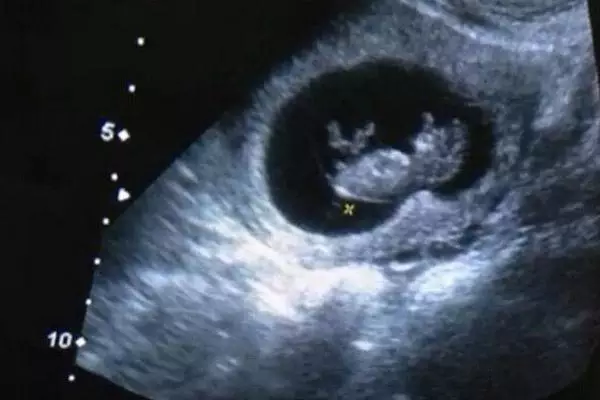

6月17日下午,台湾著名节目主持人欧弟,在微博中晒出宝宝的四维彩超照片。“跟老天爷又申请了一个账号,希望我没有的技能,他都能顺利拥有…”

上个月,同样为台湾艺人的吴佩慈也在自己的脸书上放了宝宝的超声波照片!晒宝宝照片可不仅仅在台湾艺人中流行,大陆艺人早就在微博中晒得不亦乐乎。

没错!这就是我们的嗯哼大王!2013年8月19日,霍思燕在微博上晒出了嗯哼大王的四维彩超照片,简直萌翻了!就在1个月后,9月19日上午9点,嗯哼大王出生了!

期待的过程总是焦急又兴奋,在ta降临世界之前,是否千万次幻想宝宝的样子,每次翻身,每个表情,在这里,都可以给您最真实的呈现。它不但能更清晰、更立体地把宝宝的一言一行,一举一动,生动地传达给孕妈妈,让孕妈妈和宝宝穿越时空提前“相见”。

四维彩超原价498元(院庆活动预约立减148元),仅需350元(胎儿排畸最关键一步)。

四维彩超的风靡让人们大呼过瘾,看似如此简单的设备,却有那么多的功能。当孕妇纷纷踏进医院做四维彩超的时候,b超室里同样有做检查的孕妇,这时人们不经会问:孕妇必须做四维彩超吗?做其他超声检查不行吗?